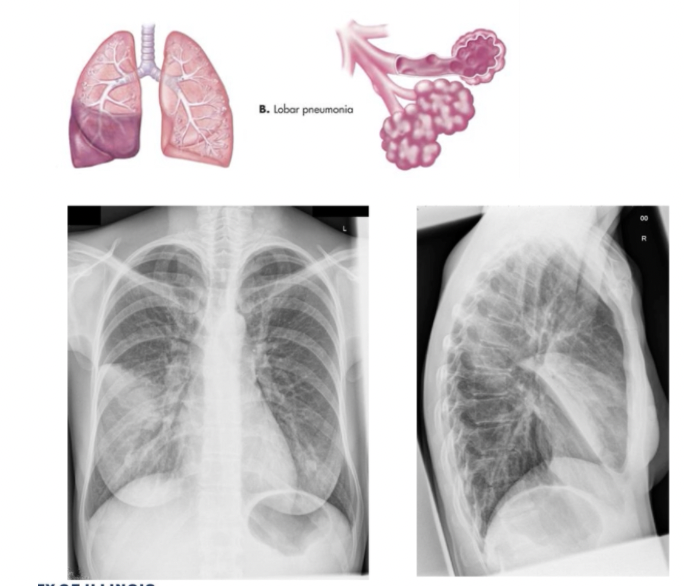

What CXR radiographic findings are typical for lobar pneumonia

Homogenous consolidation in 1 or more lobes with air bronchogram (air-filled bronchi (dark) being made visible by the opacification of surrounding alveoli) often present